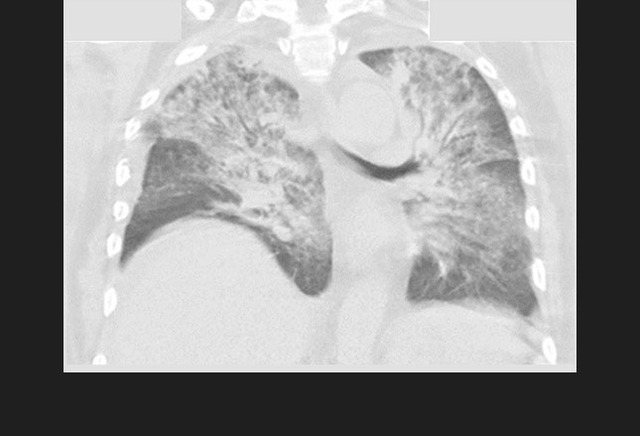

图9. 冠状位CT展示了一位结核患者右上肺的巨大空洞病变,伴随着多个小结节及空洞。

经过2个月的治疗,下列哪项提示可能是多耐药结核感染?

A、无发热;

B、无盗汗;

C、咳嗽改善;

D、体重继续减轻;

E、胸部X线无改善。

图10. 一位继发于慢性结核的患者双侧肺尖胸膜实质疤痕

答案:D、体重继续减轻。

随着有效的抗痨治疗,患者体重应当增加。当出现持续发热、胸部X线恶化、咳嗽增加、持续夜间盗汗及痰培养迟迟不能转阴时均应考虑到多耐药结核感染的可能。